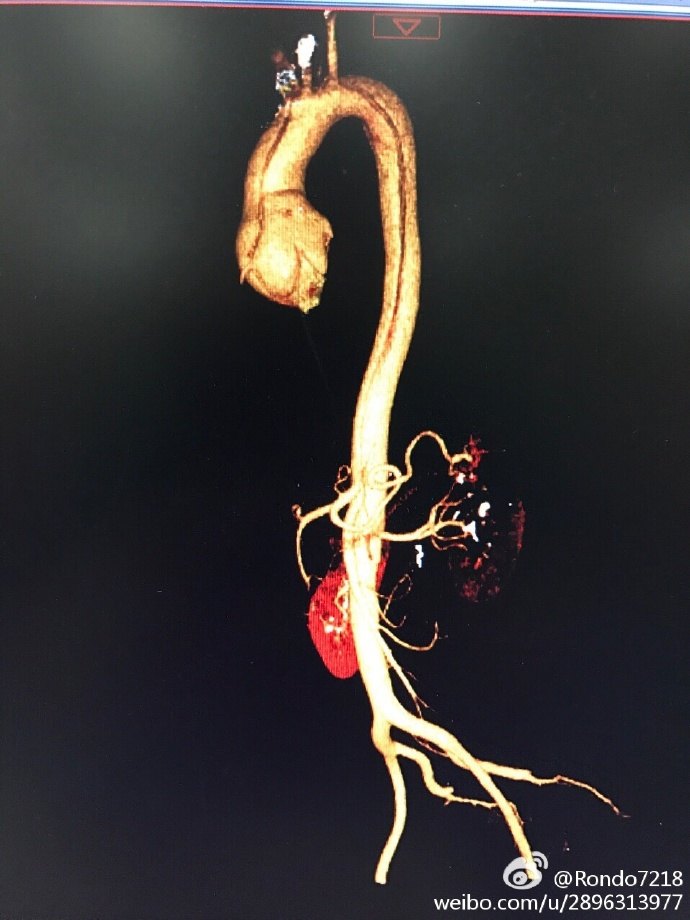

a型主动脉夹层全弓置换 "象鼻"支架置入手术

夜间急诊手术,行主动脉根部替换 主动脉全弓替换 远端象鼻支架术.